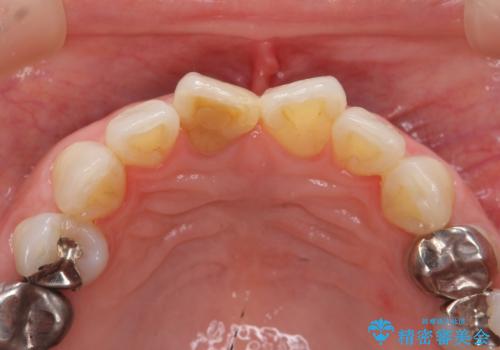

前歯の変色 セラミック審美補綴

- 前歯の変色の改善を希望され来院されました.

以前に神経が死に、根管治療を行った歯の変色が認められたためセラミックによる審美補綴治療を計画します。

神経の死んでいる歯について

神経治療を行い補綴(かぶせもの)治療を行わないと、変色が目立ち審美障害を起こすことがあります。